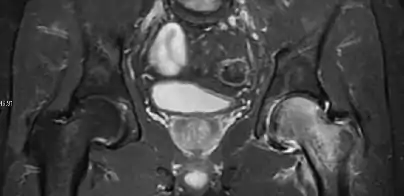

In adults, MRI is currently playing a definite role in the assessment of osteoarthritis. Although traditionally belonging to the arena of radiographs, the role of MRI has been stressed after the term femoral acetabular impingement was coined in 2003. Growing interest has been focused in accurate diagnosis of the acetabular and femoral morphological abnormalities that may lead to early osteoarthritis.[1]

MR imaging is considered paramount to these objectives, mainly when surgery is considered, due to the ability of MRI to portray the whole section of the femoral neck surface, as well as to image the labrum and articular cartilage.[1]

Diagnosis of impingement can only be achieved if, besides imaging findings, there are also clinical symptoms and positive impingement maneuvers.[1]

Most of the angles and measurements described in the plain radiograph section can be accurately reproduced on MRI. In addition, the superiority of MRI resolution with intra-articular contrast allows detection of labral and chondral abnormalities that may influence the choice of medical, percutaneous, or surgical management (Figure 9).[1]

MR arthrography has proven superior in accuracy when compared to native MR imaging. It is considered the best technique to assess the labrum. Knowledge of the normal variable morphology of the labrum helps to differentiate tears from normal variants. A triangular shape is most commonly seen in 66% of asymptomatic volunteers, but round, flattened, and absent labra can also be found in asymptomatic populations. MR arthrography has demonstrated sensitivity over 90% and specificity close to 100% in detecting labral tears. Loose bodies are demonstrated as filling defects surrounded by the hyperintense gadolinium.[1]

Association between labral tears and chondral damage has been demonstrated. This underscores the interaction between cartilage and labrum damage in the progression of osteoarthritis. Chondral damage to the posteroinferior part of the acetabulum as a contrecoup lesion occurs in approximately one-third of pincer cases secondary to persistent abutment on the anterior part of the joint leading to a slight posteroinferior subluxation. This is considered a bad prognosis sign.[1]

MR arthrography can also demonstrate ligamentum teres rupture or capsular laxity, which are debated causes of microinstability of the hip. Elongation of the capsule or injury to the iliofemoral ligament or labrum may be secondary to microtrauma in athletes. MR can demonstrate abnormalities in these cases, such as increased joint volume or a ligamentum teres tear (Figure 9).[1]

Intra-articular osseous causes of pain include several conditions: avascular necrosis (AVN), transient osteoporosis of the hip (TOH), tumors, and stress or insufficiency fractures. All these entities may present with a pattern of bone marrow edema characterized by decreased signal intensity on T1 weighted images and increased signal intensity on fluid sensitive sequences, such as fat saturated T2-weighted or STIR images. When there is no evidence of a focal lesion associated with the edema pattern, TOH is suspected. When a band of low intensity is seen inside the edematous area, the shape and length of this band become important. It is generally convex to the articular surface in the case of subchondral stress or insufficiency fractures, whereas it is concave, circumscribing all of the necrotic segment, in cases of AVN. When doubts do persist, gadolinium-enhanced MRI tends to show that the proximal portion beyond the band is enhanced in fractures but is not in AVN.[1]